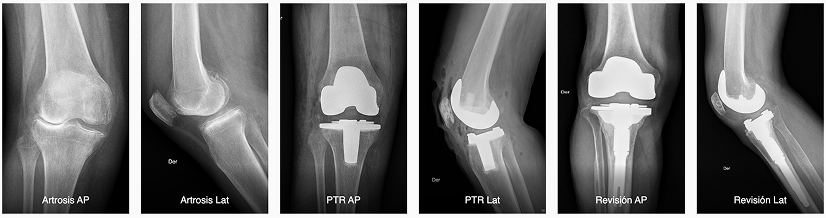

Como equipo, desde el 2020 también incorporamos la cirugía robótica de rodilla a nuestros servicios, a través del robot ROSA Knee, tecnología que asiste a los traumatólogos durante la operación y que permite devolver movilidad a la rodilla.